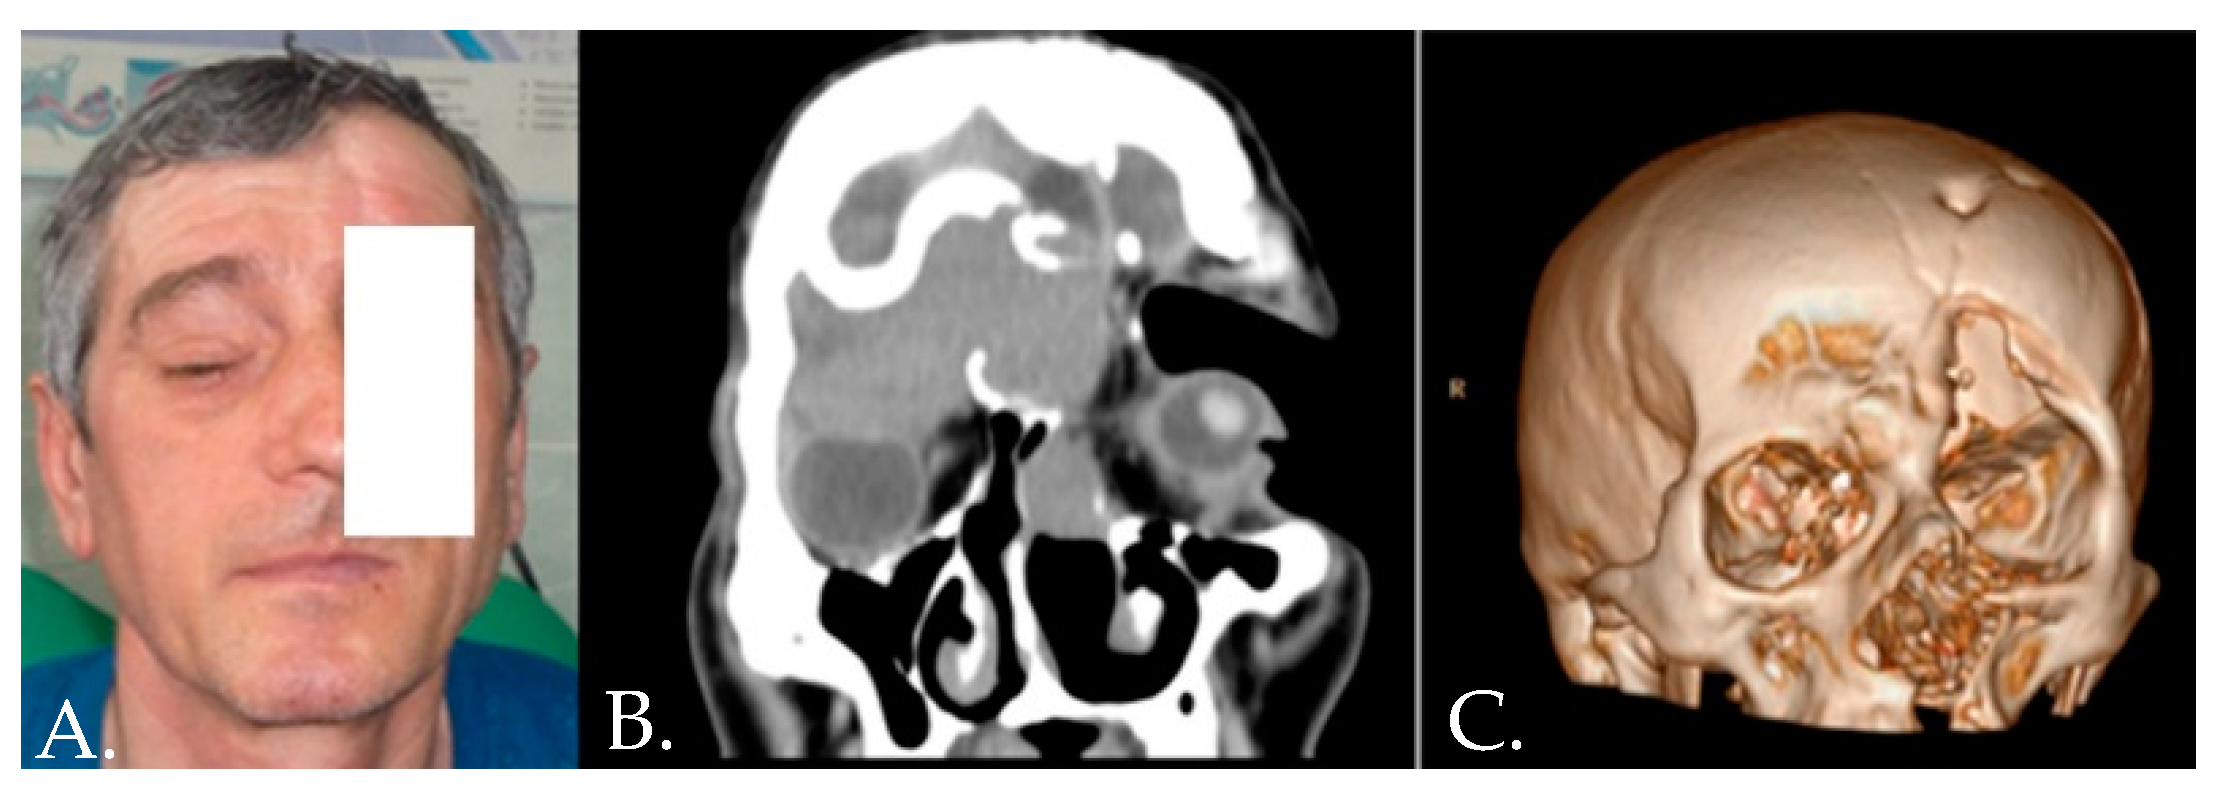

- Onișor-Gligor, F.; Țenț, P.A.; Bran, S.; Juncar, M. A Naso-Orbito-Ethmoid (NOE) Fracture Associated with Bilateral Anterior and Posterior Frontal Sinus Wall Fractures Caused by a Horse Kick—Case Report and Short Literature Review. Medicina 2019, 55, 731. [Google Scholar] [CrossRef]